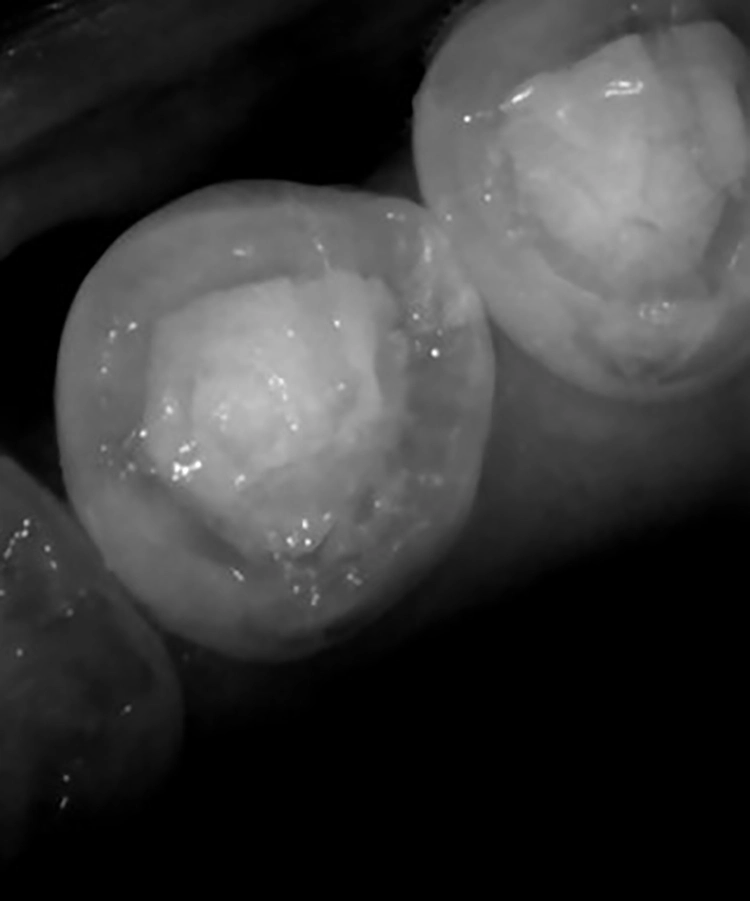

Während des Scanvorgangs erstellt der iTero Element 5D nicht nur eine sehr genaue dreidimensionale Abformung des Patientenkiefers, sondern nimmt auch simultan Nahinfrarotaufnahmen der Zähne vor. Die sogenannten Near-Infrared-Imaging-(NIRI-)Aufnahmen können anschließend gemeinsam mit dem Patienten besprochen werden.

Hell erscheinende Bereiche im Approximalraum zeigen kariöse Läsionen an. Diese sind nicht nur vom Patienten gut zu erkennen (Abb. 3 und 4), sondern tragen auch zum besseren Verständnis der Behandlungsnotwendigkeit bei.

Eine Studie [1] über die Aussagekraft dieser Aufnahmen des Approximalraumes hat ergeben, dass gerade bei initialen Läsionen die Kariesdetektion durch den Intraoralscanner iTero Element 5D genauer ist als bei der Verwendung von Bissflügelaufnahmen. Diese Technik ist ausschließlich im iTero Element 5D verbaut.